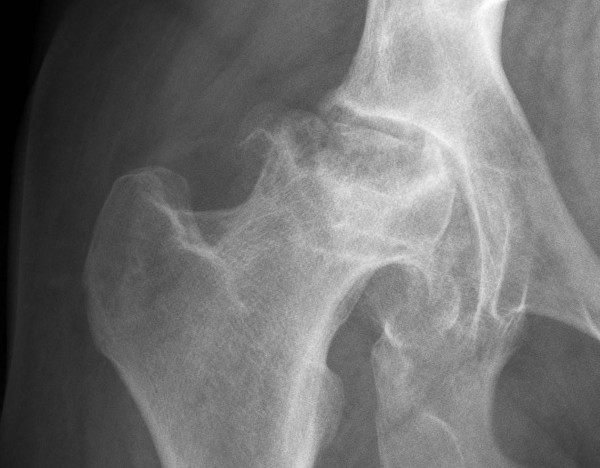

Рентгенография тазобедренного сустава в 2-х проекциях

Процедура дает возможность детально изучить особенности деструктивного процесса, обширность и конфигурацию очага. Для улучшения визуализации пораженного сустава пациента укладывают на манипуляционном по методу Лаунштейна.

В зависимости от клинической необходимости применяют I или II вариант размещения – в положении лежа на спине с согнутой под углом 45° в тазобедренном сочленении конечностью либо с отведением в противоположную естественной ротации сторону.

Рентгенографическое обследование в 2-х проекциях предназначено для получения ряда диагностических снимков, на которых отчетливо заметны участки уменьшенной плотности под субхондральной структурой.

Поверхность патологически измененных костей выглядит истонченной, покрытой микротрещинами. Анатомические деформации сочетаются с выраженным омертвением органических тканей.

Такие нарушения на рентгеновском снимке выглядят плотным затемнением, окруженным светлым ободом разной толщины. Обследование в 2-х проекциях дает возможность изучить характерные признаки деформирующего артроза. Стоимость рентгенографии в коммерческой клинике не превышает 700 руб. без учета цены расходных материалов.